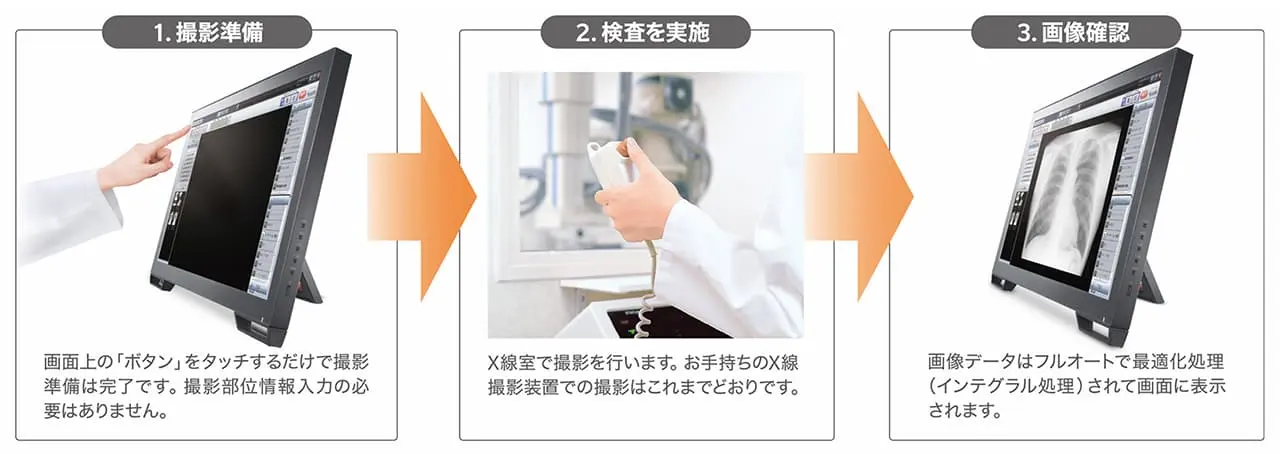

・シンプルな撮影フローの実現 「インテグラル処理」

撮影部位情報に依存しない新画像処理アルゴリズムを搭載。

・様々な読影支援機能で診療をサポート